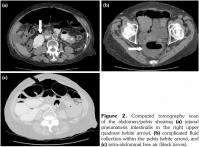

An abdominal computed tomography (CT) scan revealed large volume intra-abdominal free air, moderate intra-abdominal free fluid with no extravasated contrast, pneumatosis of the proximal jejunum with dilatation up to 5.8 cm, and a transition point (Figure 2). These findings raised concern for acute bowel ischemia, volvulus, and possible perforation.

However, given the patient’s comorbidities, stable condition and lack of peritonitis, the general surgeon recommended conservative management with intravenous fluids and bowel rest. A repeat CT scan on post-admission day two revealed resolution of the pneumatosis and focal volvulus, but persistent intra-abdominal free air and free fluid. She was started on oral amoxicillin and metronidazole for possible SIBO and discharged on post-admission day three. She was reviewed in clinic shortly thereafter, at which point her clinical condition remained stable.